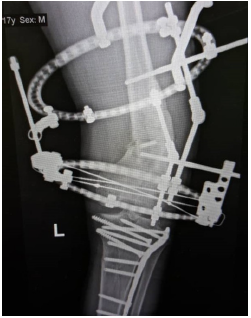

He underwent removal of implant, corrective osteotomy, left Illizarov external fixation and gradual deformity correction (Figure 3). Intra- operatively there was no local signs of infection to the distal femur and intra- operative cultures came back nil of growth/ organism. At ten weeks post-operative the deformity was corrected (Figure 4).